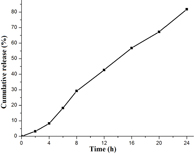

Standard image High-resolution imageDSC and XRD studies are carried out to determine whether the drug was incorporated in the nanoparticulate system as crystalline, amorphous, or bound form. The DSC thermograms demonstrated that only native hesperetin had an endothermic peak of melting point at 230 °C, whereas hesperetin-loaded nanoparticles had no such peak, which showed encapsulated HET to be in either amorphous form or in disordered crystalline phase (figure 5(a)). Furthermore, x-ray diffraction patterns of native HET and HETNPs are present in figure 5(b). Native HET has displayed the characteristic crystalline peaks of 2θ value of 14.400°, 17.212°, 21.165°, 23.760°, 26.503° and 29.720°. However, no characteristic crystalline peaks were observed when the drug was encapsulated in NPs (figure 5(b)). This indicates that the drug was molecularly dispersed or in an amorphous state, which favors easy diffusion of drug molecules through the polymeric matrix, resulting in sustained release of the drug from the nanoparticles. Sustained release of the drug from nanoparticles is an important parameter for developing successful formulations. HETNPs showed a biphasic drug-release pattern that was characterized by an initial rapid release of approximately 29.1% of drugs in the first 8 h, followed by a slow and continuous release of approximately 81.8% drug release in the next 24 h (figure 6). The observed initial release of hesperetin might be due to a rapid release of some drug loosely bound on the surface of the nanoparticles by a mechanism of diffusion. The initial rapid release was followed by a slower sustained release of hesperetin present inside the core of the nanoparticles. A similar trend of release was observed by our previous studies [23].

Standard image High-resolution imageFigure 6. Cumulative in vitro release profile of native HET from nanoparticles.

Characterization of the physiochemical properties of the drug encapsulated within the nanoparticles may possibly reveal useful information for the feasibility of using nanoparticles for cancer therapy. FT-IR results confirmed that drug is encapsulated inside the polymer. DSC results of HET showed a sharp endothermic peak at 230 °C which is the well known melting point of hesperetin, but in the case of HETNPs the melting peak totally disappeared evidencing the absence of crystalline drug in the nanospheres samples, at least at the nanosphere surface level. Therefore, it could be concluded that hesperetin in nanospheres was in an amorphous or disordered crystalline phase of molecular dispersion or a solid solution state in the polymer matrix after the production [38]. Further, this result is very well supported by XRD. Both DSC and XRD results confirmed that HETNPs have amorphous form. Encapsulation efficiency of hesperetin has increased because the hydrophobic portion of PVA interpenetrated into Eudragit chains during nanoprecipitation and remained to be trapped to the polymeric matrix of the nanoparticles. Accordingly, the addition of PVA easily formed an interconnected network with Eudragit-hesperetin and thus elevated the encapsulation efficiency of the drug. In the current study, the initial rapid release of hesperetin from nanoparticles was probably attributed to either the surface-bound moieties or an aqueous environment allowing increased water penetration. Afterwards, the HETNPs manifested the sustained release characteristics that appeared to be dependent on the hydrophobicity of hesperetin incorporated in the nanoparticles. The release pattern of the drug from the nanoparticles shows that long and continuous exposure of the cancer cells to anticancer drugs of a relatively lower and safer concentration gives little chance for the tumor blood vessels to grow, thereby resulting in much better efficacy [39]. Native HET and HETNPs were further evaluated for their in vitro cellular viability assay on KB cell lines by MTT assay. MTT results showed a good discrimination in cell inhibition between native HET and HETNPs, thus illuminating the key role of NPs binding and internalization in enhancement of cytotoxic activity. Encapsulation of anti-cancer drug in nanoparticles can increase its internalization by cells into lysosomes and enhanced cytotoxicity. The higher cytotoxic effect of hesperetin-loaded nanoparticles could be attributed to the competent cellular uptake and intracellular distribution of hesperetin.